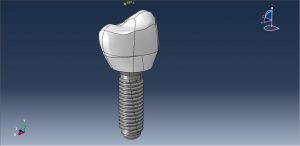

In this tutorial, Simulation dental implant in interaction with mandible bone under dynamic load in Abaqus has been investigated. The crown, Abutment, and mandible bone are modeled as three-dimensional parts. Dental implants are metal posts or frames that are surgically positioned into the jawbone beneath your gums. Once in place, they allow your dentist to mount replacement teeth onto them. Because implants fuse to your jawbone, they provide stable support for artificial teeth. Dentures and bridges mounted to implants won’t slip or shift in your mouth — an especially important benefit when eating and speaking. This secure fit helps the dentures and bridges — as well as individual crowns placed over implants — feel more natural than conventional bridges or dentures. You can see dome figures of the real and assembled parts below

The ceramic material with elastic-plastic behavior and ductile damage criterion is used for the crown. The titanium material with elastic-plastic material and Johnson-Cook damage are used to model root or abutment material. The mandible bone is modeled as an elestic-plastic material. The dynamic explicit procedure is appropriate for the dynamic loading conditions. The general contact algorithm with contact property is used to model all contact among the parts. The proper boundary condition is assigned to the mandible and concentrated force with smooth amplitude is selected for the crown. The mesh should be fine, because of the complexity of the model